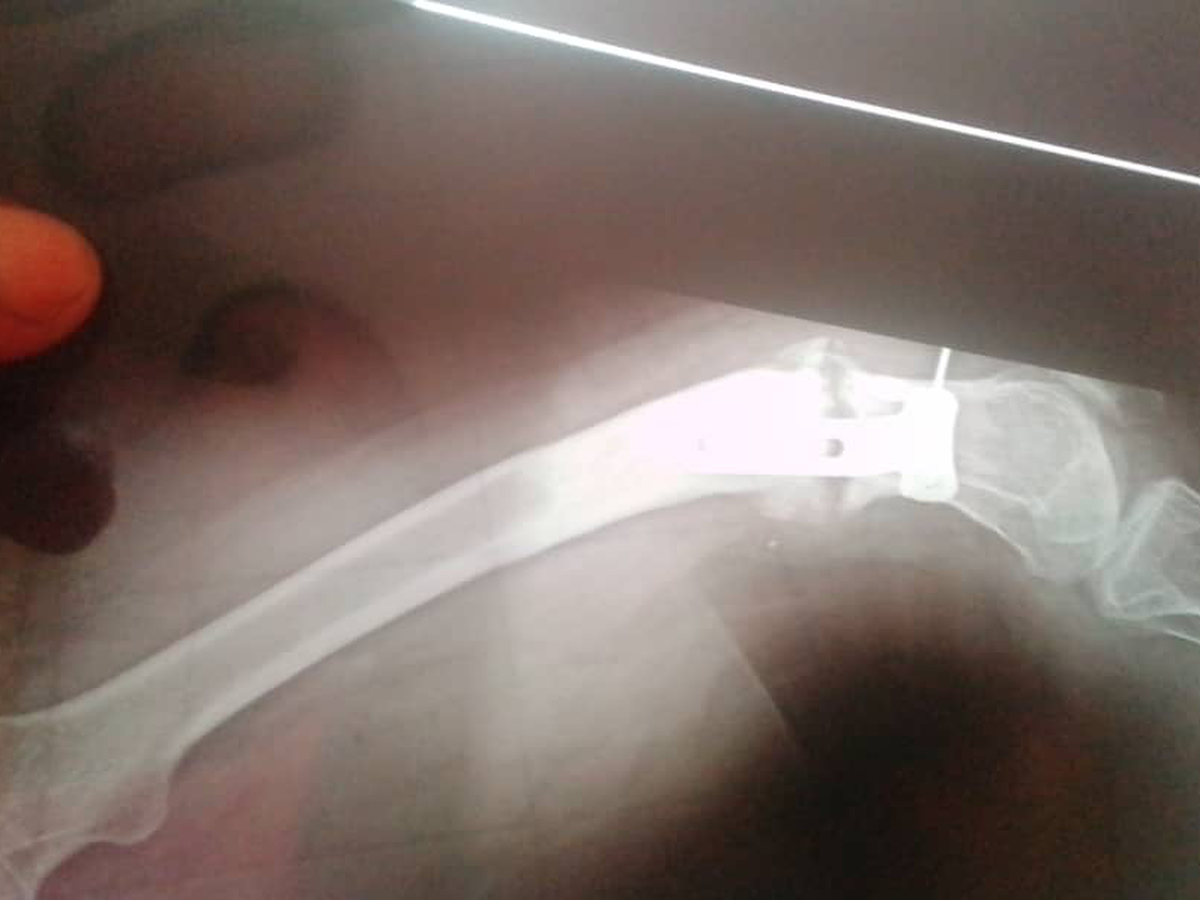

For years, I suffered in silence, unable to get proper care. Eventually, I returned to my mother’s home and began to rebuild my life. However, the pain remained, and in 2021, it intensified. To my shock, I learned that an iron implant had been in my leg for 15 years without my knowledge.

Recently, I had another surgery, thanks to the support of a wonderful woman named Mum Shantal. Unfortunately, the procedure did not go as planned. The surgeon was supposed to straighten my bent leg, but they failed to properly lock the bone in place. As a result, I am now in even more pain, and my condition is worse than before.

I visited another hospital for a second opinion, where a doctor explained that the previous surgery was done incorrectly. I need a complex and crucial operation to correct the mistakes, which involves removing bone from my waist and inserting it into my leg. This is the only option for my body to support my leg properly and alleviate the constant pain.